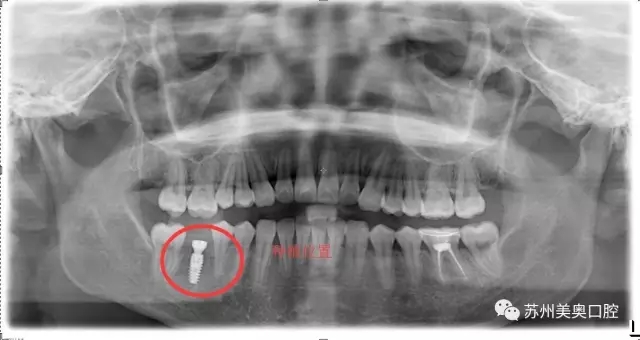

光学显微镜主要用于放大微小物体成为人的肉眼所能看到的仪器,所以被广泛应用于医学研究和临床手术中。口腔显微种植高精度可以精确到1毫米,将细微的口腔解剖结构放大近30倍,患者看到的下图仅仅放大了10倍。

相比于传统肉眼观察,显微口腔治疗为医生提供了聚焦光源和放大的清晰视野,明确分辨微小的神经血管,便于医生更换更小更精密的工具,进行的治疗,让种植牙更加安全高精。苏州美奥显微口腔治疗利用现代医疗科技一步一步实现着口腔治疗微观高精化。